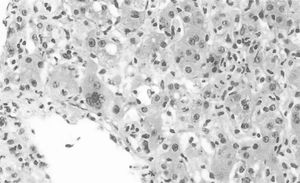

Materials and PatientsA 43-year-old woman with no history of alcohol, herbal, or drug consumption. She presented with asthenia, adynamia, and unquantified fever, self-medicating with ibuprofen 1.2 g/day. Subsequently, she developed right hypochondrium pain and generalized jaundice without discontinuing ibuprofen. Four weeks after the onset of symptoms, she developed choluria, acholia, and hyporexia, with laboratory findings showing mild thrombocytopenia (platelets 109,000 u/L), transaminasemia (aspartate aminotransferase 890 U/l, alanine aminotransferase 1183 U/l, alkaline phosphatase 311 U/l), direct hyperbilirubinemia (total bilirubin: 7.8 mg/dl, direct: 6.8 mg/dl), and prolonged prothrombin time. Hepatotropic virus and HIV infections were ruled out, as well as autoimmune liver diseases. Hepatic ultrasound showed a starry sky pattern and splenomegaly. Magnetic resonance cholangiopancreatography revealed only hepatosplenomegaly. Liver biopsy showed intense inflammation with polymorphonuclear and lymphocytic infiltrate, total acinar involvement, cholestasis, and hepatocellular necrosis, compatible with acute severe hepatitis and accentuated cholestasis probably secondary to DILI. Management with ursodeoxycholic acid and prednisone (50 mg/day) was initiated without improvement, with a torpid evolution due to the development of hepatic encephalopathy, coagulopathy, and upper gastrointestinal bleeding.

Figure 1. Liver biopsy from the patient

Giant cells, cholestasis, Kupffer cells and hepatocelular necrosis were identified